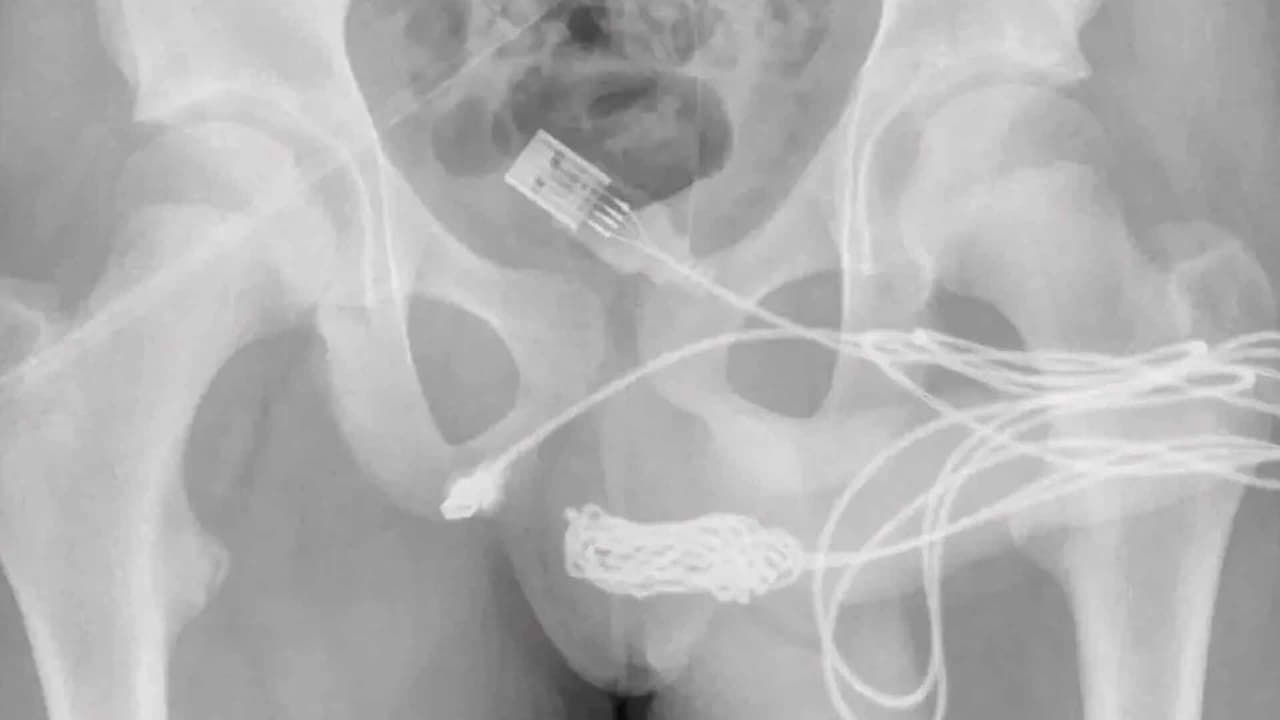

El joven de 15 años, tuvo que someterse a una cirugía tras ser provocado por la curiosidad de conocer la medida de su parte íntima y el cable se quedara atorado en su uretra.